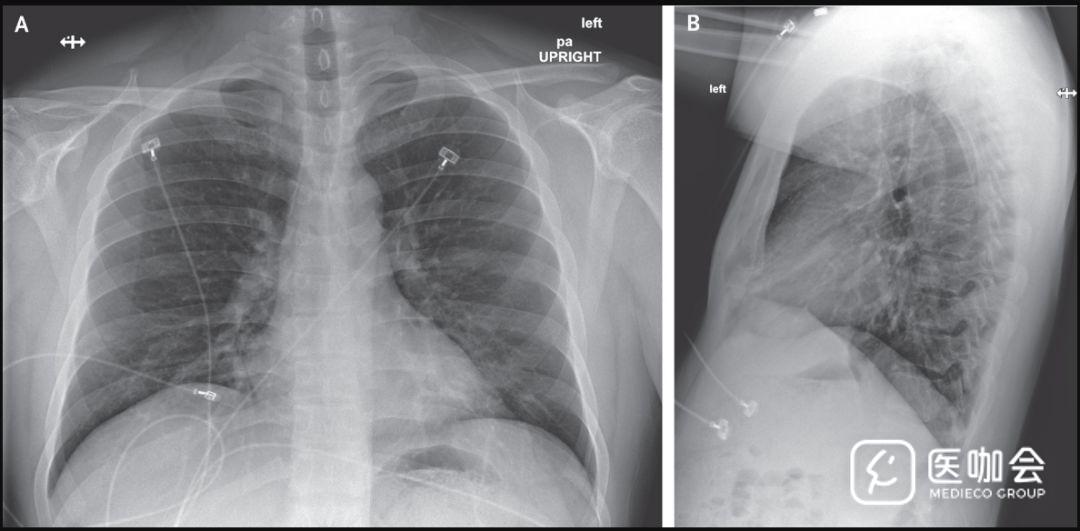

住院第6天(患病第10天),胸片显示两肺均有基底区条状阴影,与非典型肺炎相符(图5),且听诊时两肺均有啰音。

图5. 住院第6天(患病第10天)的胸片

患者持续高热,医生决定给予试验性抗病毒疗法。在住院第7天晚上开始静脉给予remdesivir(瑞德西韦,一种研发中尚未获批的新型核苷类似物),未观察到不良反应。当天晚上停用了万古霉素,并于第二天停用了头孢吡肟。

住院第8天(患病第12天),患者状况有所改善。患者停止吸氧,氧饱和度为94%到96%。双肺啰音已消失。患者食欲也得到改善,除了间歇性干咳和流涕外,无其他症状。